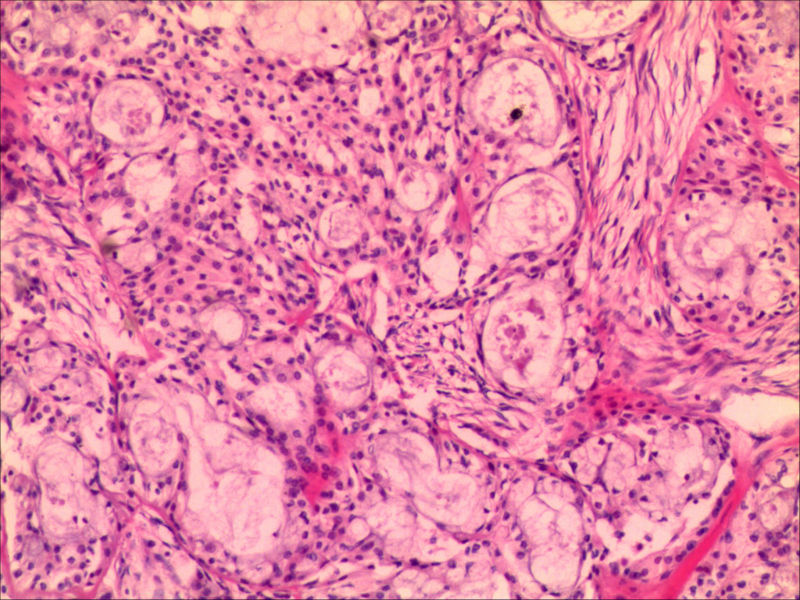

典型的黏液表皮样癌,低度恶性。

本例可以看到典型的产粘液细胞、鳞状细胞、中间细胞和透明细胞,因为产粘液细胞多,甚至形成粘液湖,加之包块似有包膜,分界清楚,应该考虑粘液表皮样癌(低度恶性)。